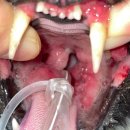

• 여울동물병원 | 용인 최고 동물병원. 24시 쓰담쓰담 치료후기

24시쓰담쓰담동물메디컬센터 경기도 용인시 기흥구 중부대로 364 2층 24시 쓰담쓰담 동물메디컬센터 구내염 심한아이 치료하였습니다. ​ 냄새나고 더러워 안받아 주는 병원도 있는데 항상 아픈 아이들 싫은 내색 없이 받아주셔서 너무 감사합니다. ​ ​ 입원하면 아침 마다 카톡으로 사진이랑 아이 상태 안내해주십니다...